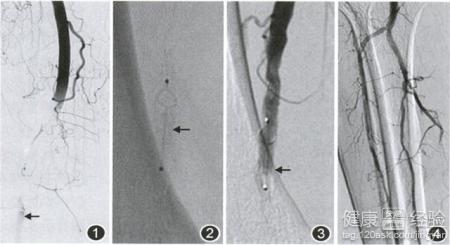

3動脈栓塞的治療方式。非手術治療,為降低血脂和血壓,接觸血液高凝狀態,從而使側支循環形成;方法有嚴格禁煙和適當運動等藥物有阿司匹林、雙嘧達膜等;手術治療有經皮腔內血管成形術,內膜剝脫術,旁路轉流術等。